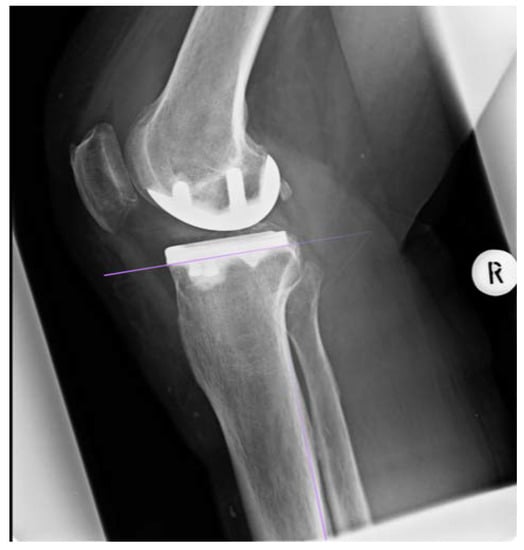

The posterior inclination of the tibial component was determined from the lateral radiographs according to Faschingbauer et al. [13]. One tangent was applied to the posterior cortex, another to the caudal end of the component. Thus, the angle was calculated between the two lines. This process of measurement is shown in Figure 5.

Figure 5. Illustration of the measurement process. For determining the posterior slope, a tangent was drawn next to the posterior cortical axis, another one next to the lower border of the tibial component. In this case the posterior inclination was 87.5°.